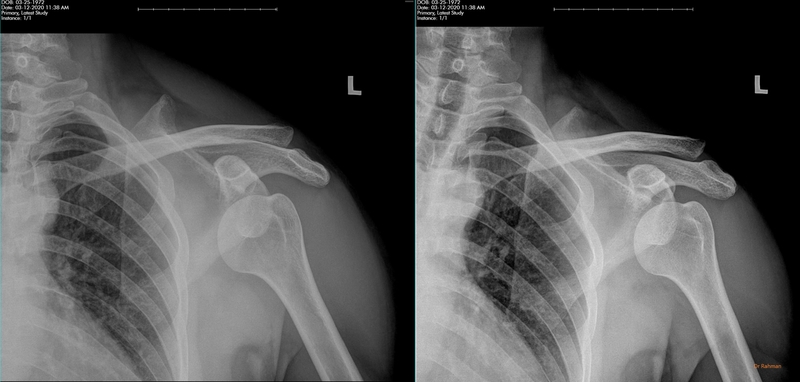

Trật vai ra trước

Chiếm 95% các trường hợp trật khớp vùng vai, chỏm xương bị lật ra trước ổ chảo xương vai, có thể hướng xuống dưới hoặc vào trong. Các dạng cụ thể gồm chỏm ngoài mỏm quạ (bán trật), chỏm dưới mỏm quạ, chỏm trong mỏm quạ và chỏm dưới xương đòn.

Trật vai trước chiếm khoảng 95% các trường hợp trật khớp vai

Hình ảnh X-quang trật khớp vai trước